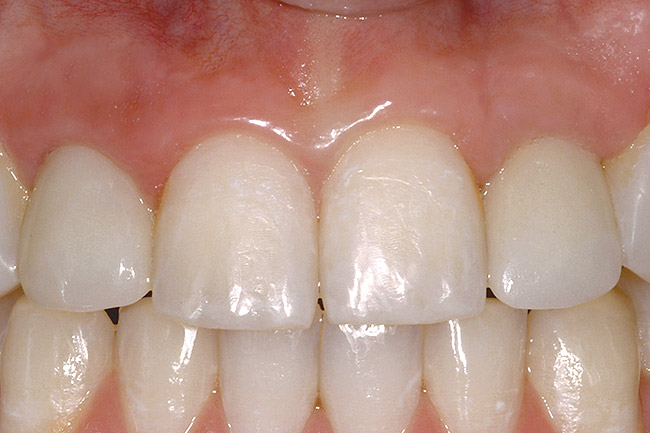

The transitional titanium abutments were left in place for 8 weeks. During this time, the morphologically shaped, computer-milled abutments supported the interproximal tissue and developed the desired emergence profiles. The computer-milled abutments were created to accommodate the adjacent teeth and opposing occlusion, and to aid in the fabrication of the final porcelain-fused-to-metal (PFM) restorations (Figure 41 and Figure 42). The final crowns were delivered 4 months after implant placement. The radiograph of the emergence profile confirmed the seamless fit of the abutment-implant-crown interfaces (Figure 43). The final restorations were esthetic, functional, and met the needs of the patient (Figure 44). The re-establishment of the interdental papilla completed the careful transformation of the flat alveolar crestal tissue into a proper emergence of the clinical PFM crowns, indistinguishable from the surrounding dentition (Figure 45).

Figure 44  FINAL RESULTS The final restorations are indistinguishable from the surrounding dentition, demonstrating good emergence and re-creation of the interdental papillae.

Figure 44

Figure 45  FINAL RESULTS The final restorations are indistinguishable from the surrounding dentition, demonstrating good emergence and re-creation of the interdental papillae.

Figure 45